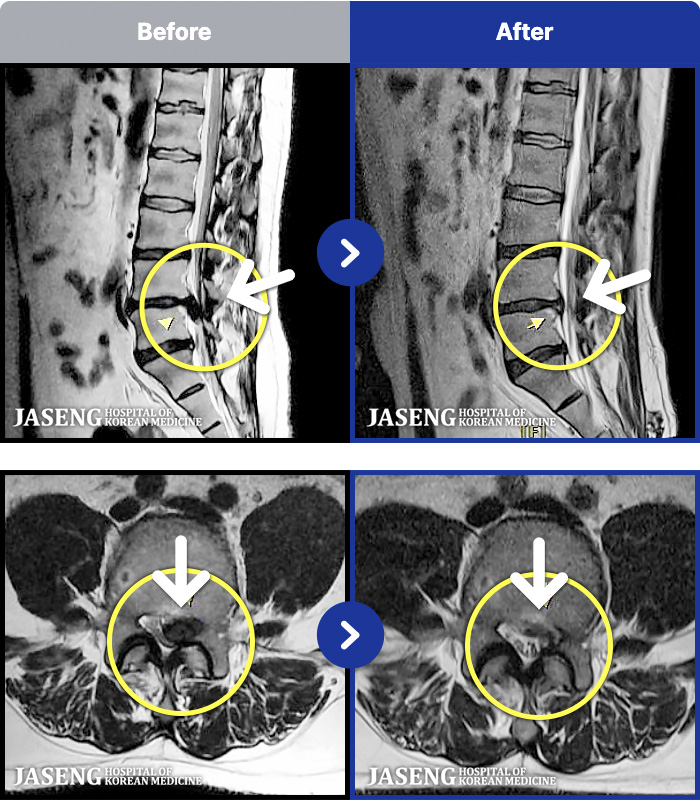

MRI ġ

1,301 MRI ũ ʸ Ȯϼ.

Ƹ ϰ ־.